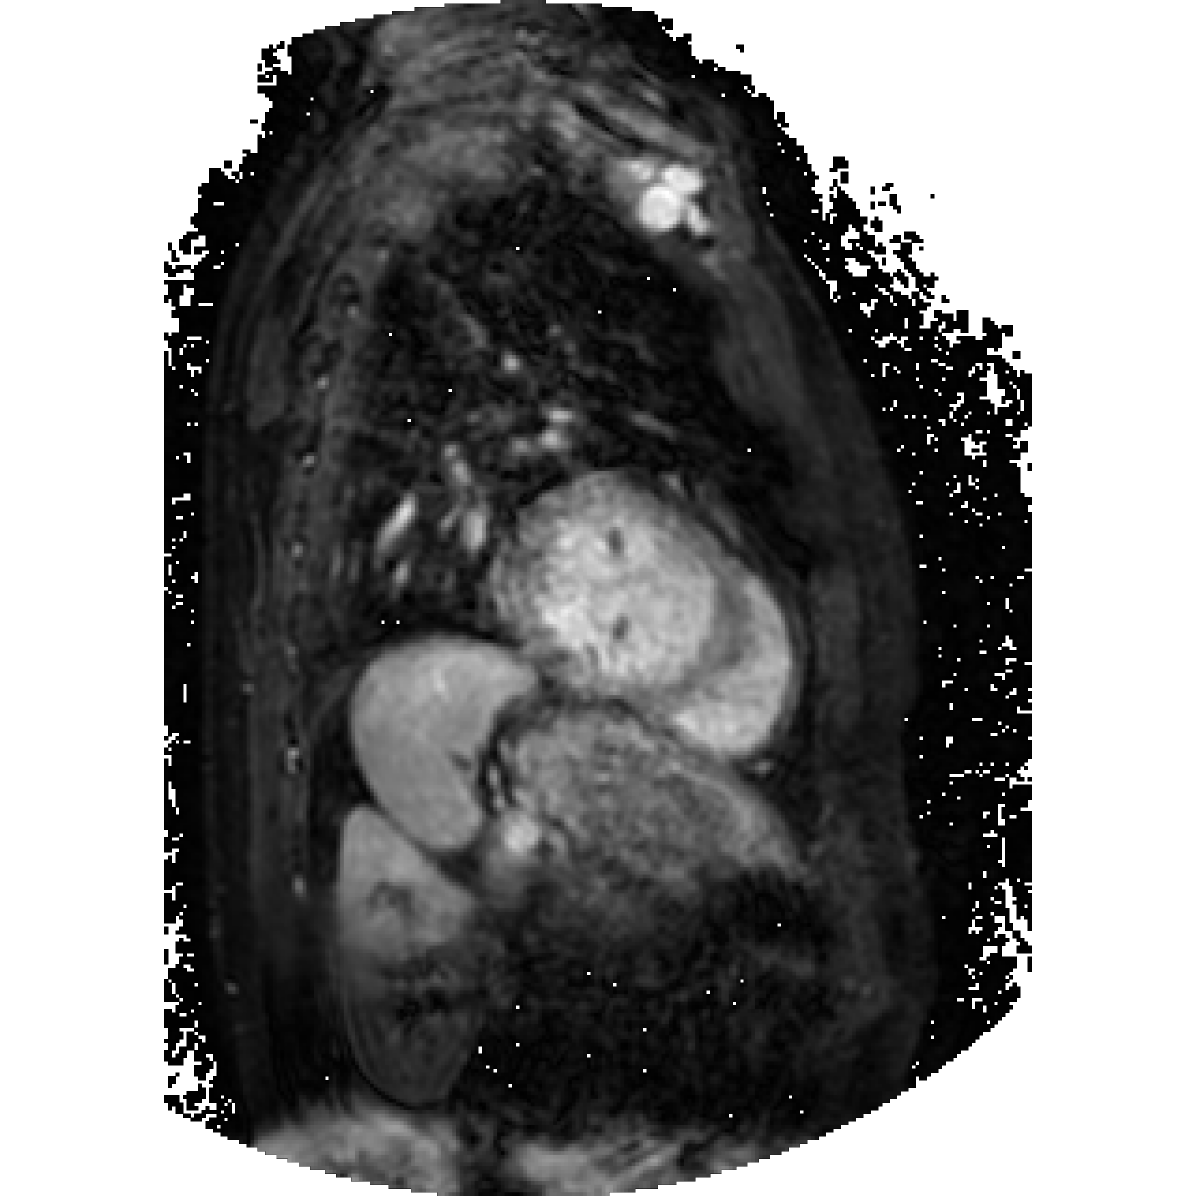

Figure 2: PCA component visualization. Following [8], the PCA is computed between patches of images that are in the same column, and the first 3 components are shown. This is done for X-ray, CT, and MRI scans. Thresholding is used on the first component to remove the background.

In this section we will show qualitative results of DINOv2 features using principal component analysis (PCA) performed on DINOv2 patch features on X-ray, CT, and MRI scans, following the method delineated in [8]. We will also provide organ segmentation results of linear compared U-Net decoders.

PCA visualization. Figure 2 shows the first three PCA components. The PCA is computed between patches of images that are in the same column, and the first 3 components are shown for X-ray, CT, and MRI scans. Thresholding is used on the first PCA component to remove the background. Just like in natural images [8], the colors of the three PCA components correspond well with the same parts of images in the same category. This is an easier task however, compared to natural images, because there is less variability between examinations on medical images compared to natural images.